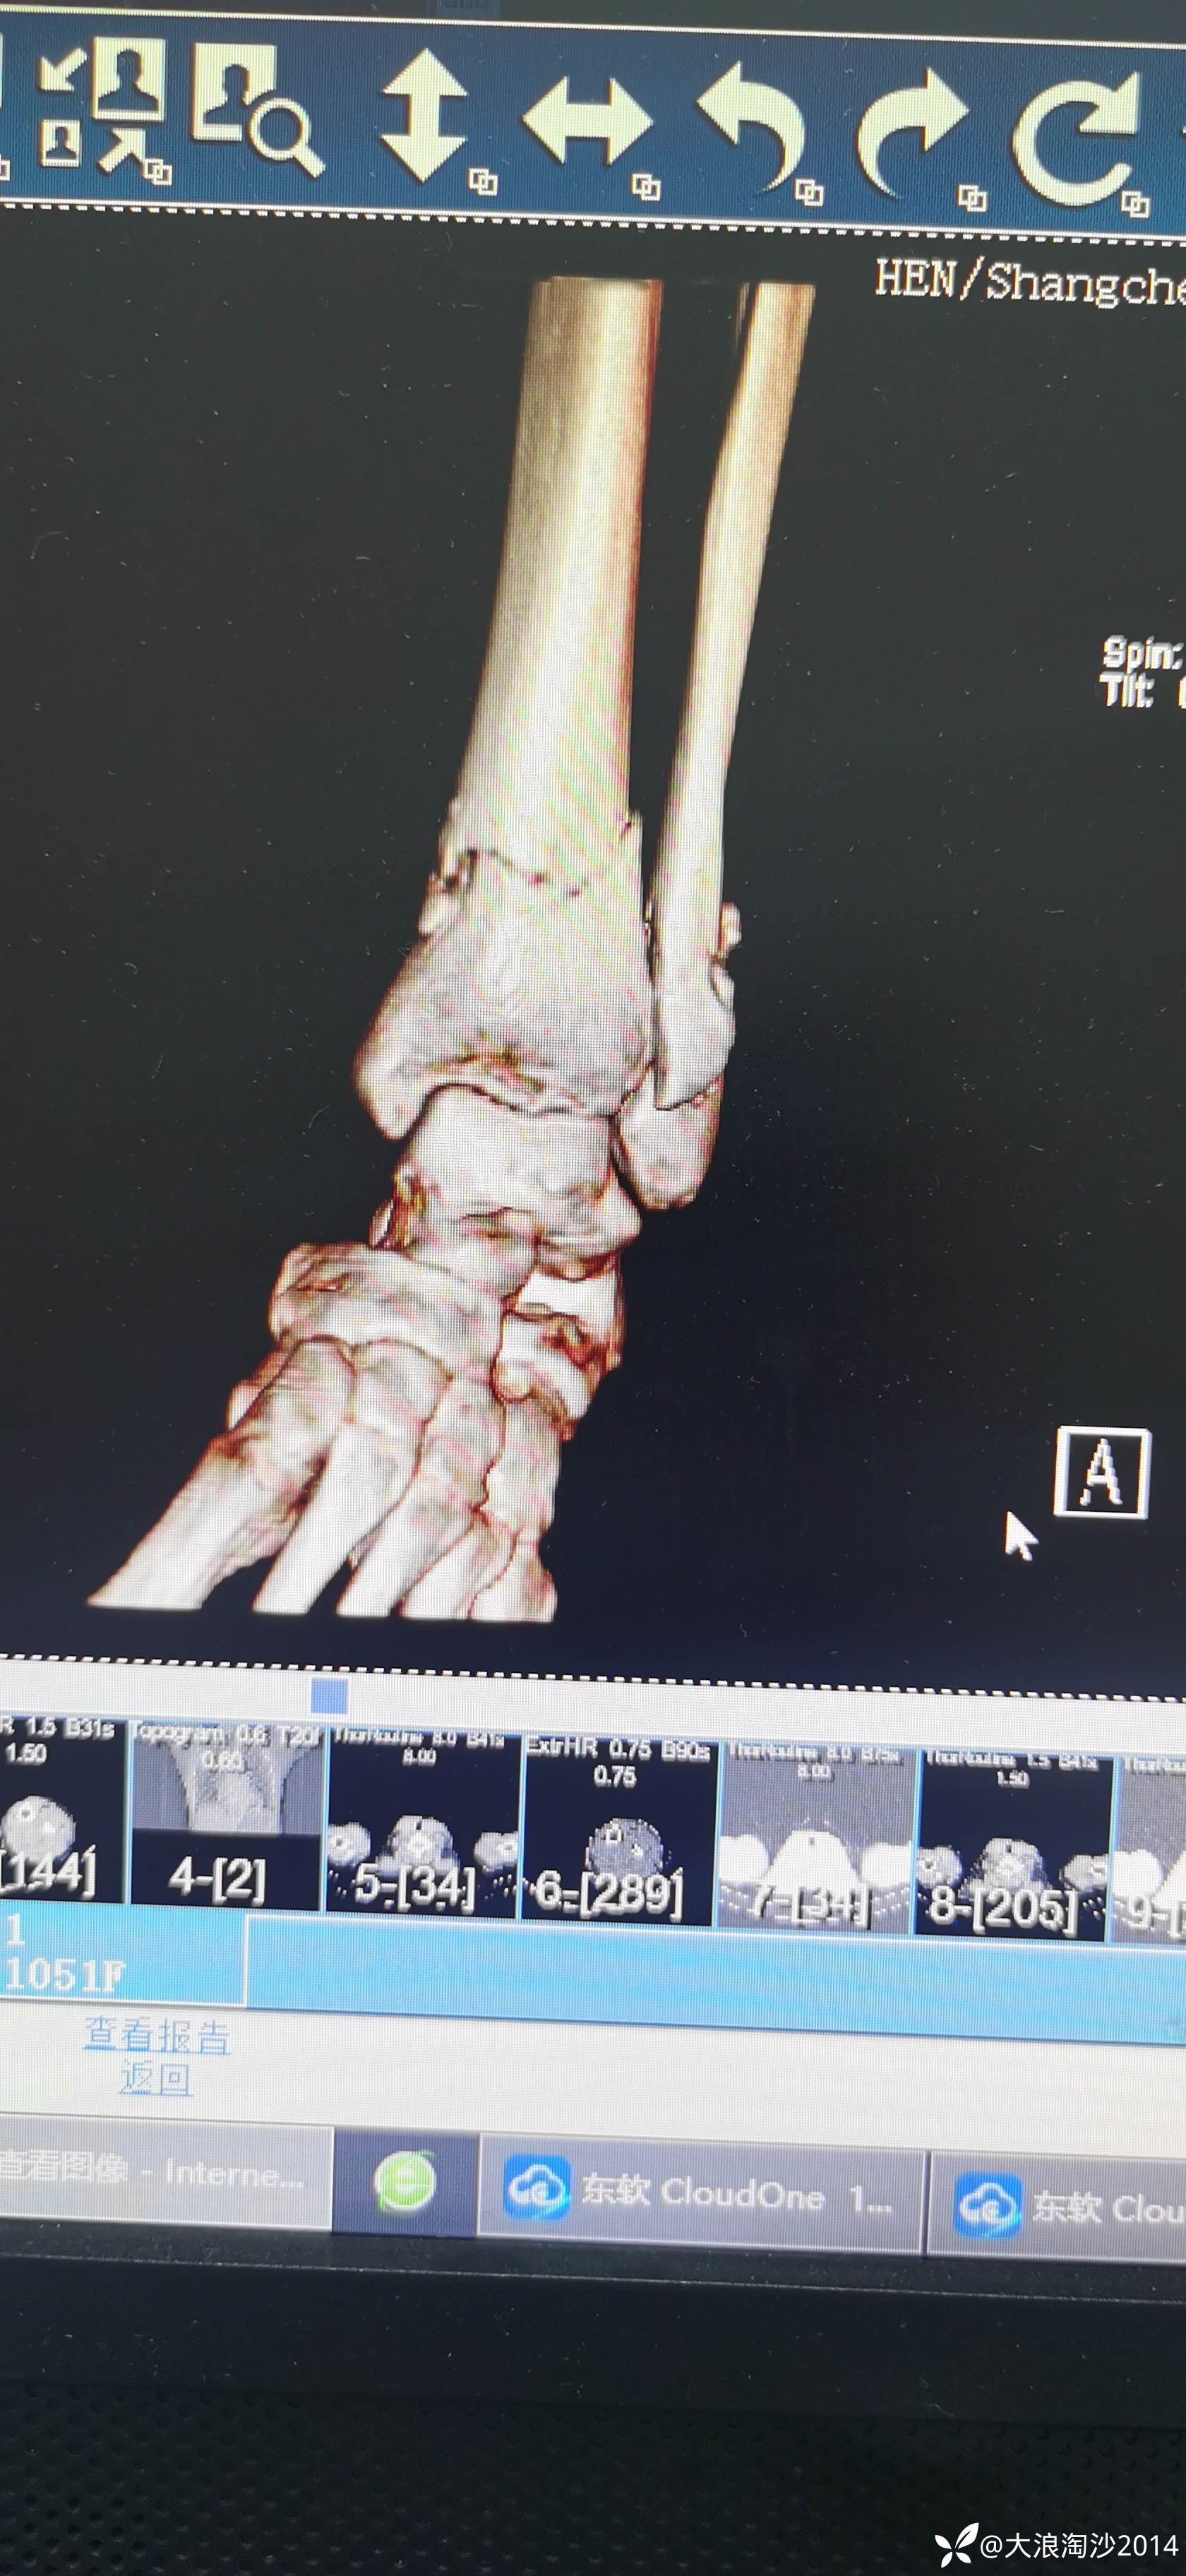

一65岁女性患者,偏瘦,体重75斤,车祸外伤致左胫腓骨远端骨折,入院后消肿后,病人可以用皮包骨头形容,考虑胫骨远折端不适合用内侧插板(mippo技术),病人太瘦,如取两个切口分别处理胫腓骨,切口容易出现问题,因此采用前外侧一个切口处理胫腓骨远端骨折(片子顺序上传有点乱)